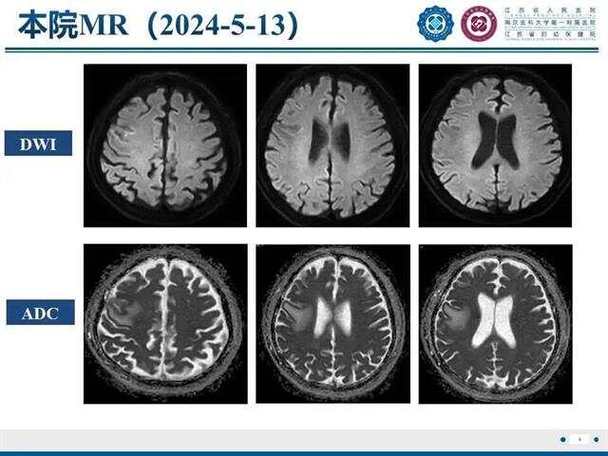

DWI图像上怎么看结果?

在看DWI图像时,我们通常会同时看另一张图像,叫做ADC图 (Apparent Diffusion Coefficient,表观弥散系数图)。

DWI像:

- 正常脑组织:呈中等灰色信号。

- 急性梗死区域:由于水分子运动受限,信号会显著增高,表现为“亮白”的病灶,这是最直观的诊断依据。

ADC图:

(图片来源网络,侵删)- 正常脑组织:呈中等灰色信号。

- 急性梗死区域:因为水分子扩散受限,其表观弥散系数值会降低,在ADC图上表现为“变黑”。

简单记忆:

- DWI像上“亮白” + ADC图上“变黑” = 典型的急性脑梗死,这个组合被称为“弥散受限”,是诊断急性脑梗死的标志性表现。

为什么需要ADC图? 主要是为了鉴别,有些其他情况(如肿瘤、感染)在DWI上也可能呈高信号,但ADC图上不一定会变黑,ADC图可以帮助区分急性期和慢性期的梗死。